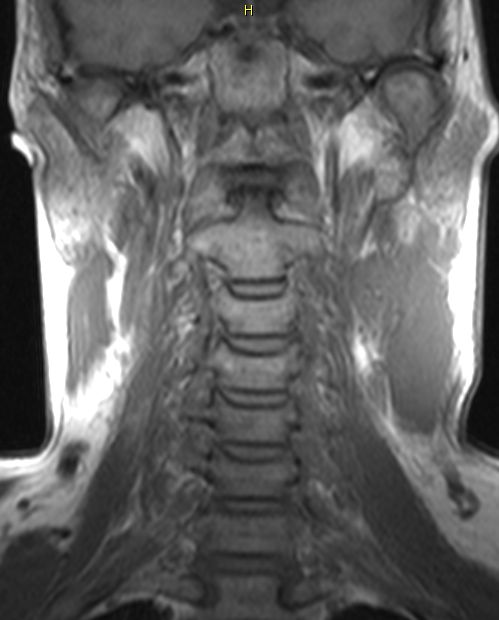

Hals-CUP 49jährige Frau mit Metastasen eines schleimbildenden Adenokarzinoms.